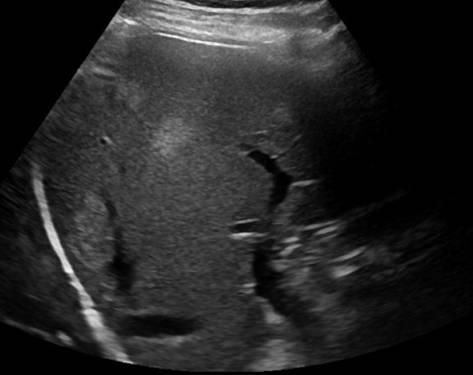

Gan nhiễm mỡ

» Thông tin: Nam giới – 42 tuổi.

» Lâm sàng: Kiểm tra sức khỏe.